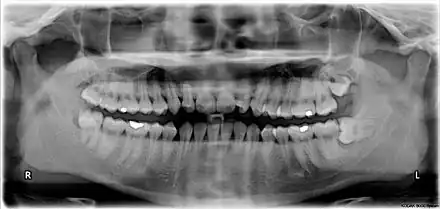

The third molar, commonly called wisdom tooth, is the most posterior of the three molars in each quadrant of the human dentition. The age at which wisdom teeth come through (erupt) is variable,[1] but this generally occurs between late teens and early twenties.[2] Most adults have four wisdom teeth, one in each of the four quadrants, but it is possible to have none, fewer, or more, in which case the extras are called supernumerary teeth. Wisdom teeth may become stuck (impacted)[3] and not erupt fully, if there is not enough space for them to come through normally. Impacted wisdom teeth are still sometimes removed for orthodontic treatment, believing that they move the other teeth and cause crowding, though this is no longer held as true.[4][5]

Wisdom teeth (often notated clinically as M3 for third molar) have long been identified as a source of problems and continue to be the most commonly impacted teeth in the human mouth. Impaction of the wisdom teeth results in a risk of periodontal disease and dental cavities.[29] Impacted wisdom teeth lead to pathology in 12% of cases.[30]